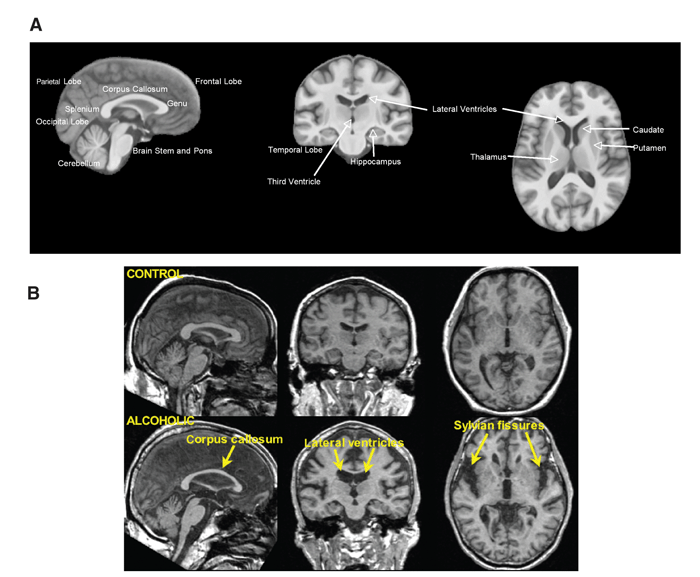

Many researchers believe that the entire brain is involved with memory, in some way or another (Lashley, 1950). However, some key areas have been identified (shown below in Figure 1.) and include the amygdala, hippocampus, cerebellum, the prefrontal cortex and the synapses linking them all (Mayford, Siegelbaum, & Kandel, 2012).

Amnesia is essentially the instances where memory, or the process of forming memories, fails. The processes of forming, maintaining and recalling memories is extremely complex and as mentioned above involves numerous brain structures, if not the brain in its entirety. This can lead to numerous points of failure and thus numerous reasons for memory to fail; leading to amnesia.

In terms of understanding amnesia and memory, the convoluted and complex nature of the memory process can make it difficult to pinpoint which areas are responsible for which functions, this problem is also relevant when looking at the symptoms of amnesia which quite often include several deficits outside those of memory. These are referred to as ‘comorbid’ symptoms, diseases or conditions that occur alongside another disorder, and can make it difficult to differentiate the issues that are a direct result of amnesia and those that are not. Examples of those that appear alongside amnesia would be perceptual deficits and confabulation; this is often associated with WKS and will be further described in the ‘Signs/Symptoms’ section below.

However, as research has developed, and the mapping of the brain and its functions has developed researchers are becoming able to pinpoint the structure’s role within memory, such as the amygdala facilitating the encoding of memories to a more significant degree when the event is emotionally arousing (Josselyn, 2010). This means that when an individual suddenly fails to respond to stimuli that normally would have induced a fear response; a neurologist can narrow down their investigation and begin imaging of the amygdala with the expectation of some sort of abnormality (e.g. a lesion or tumour) affecting it’s functioning.